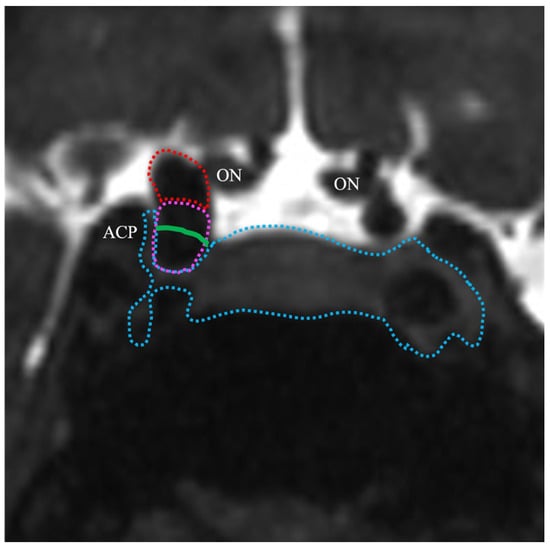

2.4. TS–ACP Line Method

2.5. Image Analysis

4.1. Anatomical Basis and Technical Considerations